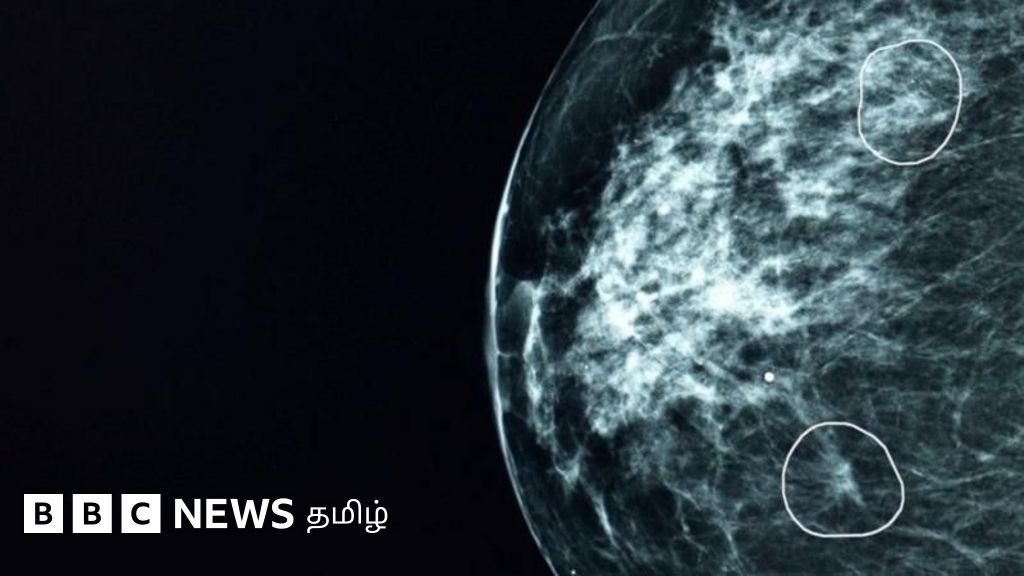

மருத்துவர்களால் பார்க்க முடியாத புற்றுநோய் கட்டிகளை கண்டறியும் 'மியா'

பிரிட்டிஷ் மருத்துவமனைகளில் பரிசோதிக்கப்பட்ட ஒரு செயற்கை நுண்ணறிவு (AI) கருவி, மருத்துவர்களால் கவனிக்கப்படாமல் போன 11 பெண்களில் மார்பக புற்றுநோயின்